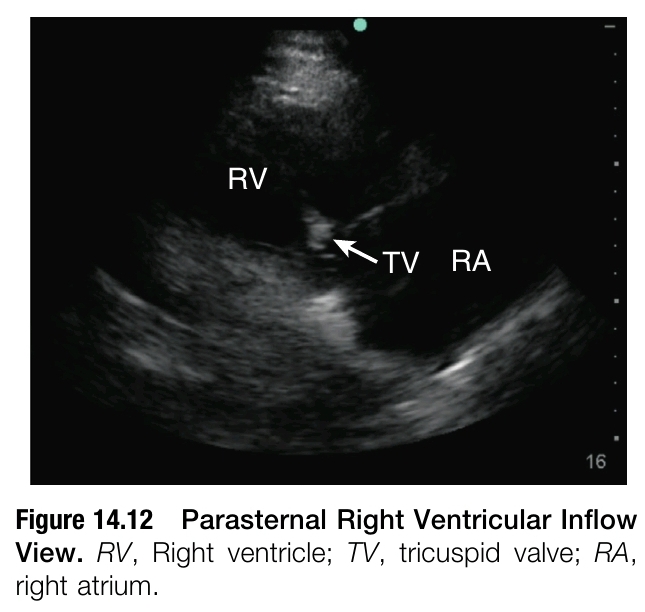

PARASTERNAL RIGHT VENTRICULAR INFLOW VIEW

PLAX에서 right venticlular(RV) inflow view는 transducer가 환자의 right hip을 향하도록 tilting 함으로써 얻을 수 있다. Ideal RV inflow view는 LV가 조금도 보이지 않도록 하면서 RV, RA, TV를 보여준다(figure 14.12). 이 view에서 TV의 posteiror leaflet을 볼 수 있고 tricuspid regurgitation(TR) 평가를 할 수 있다. 만약 LV의 일부분이 보인다면, septal leaflet를 posteior leaflet으로 오인할 수 있다. TR 환자에서 spectral Doppler를 이용하면 pulmonary artery systolic pressure의 확인을 위해 valve 위아래의 pressure gradient를 측정할 수 있다.